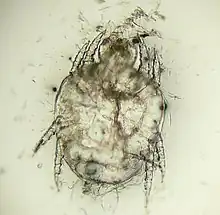

| Cheyletiella yasguri (?) from a dog | |

Cheyletiella is a genus of mites that live on the skin surface of dogs,[2] cats,[3] and rabbits.[4]

The adult mites are about 0.385 millimeters long, have eight legs with combs instead of claws, and have palpi that end in prominent hooks.[5] They do not burrow into the skin, but live in the keratin level. Their entire 21-day life cycle is on one host. They cannot survive off the host for more than 10 days.[6]